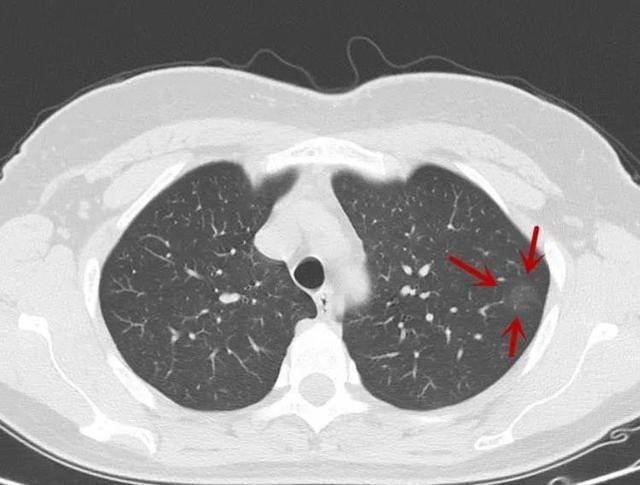

双肺小节结,建议随访观察,是什么意思?

今天走进其他恶性肿瘤主题课堂一起学习相关病例肺结节交互印证式诊断

医生直言肺部有结节的人建议多吃2物或有助结节消散